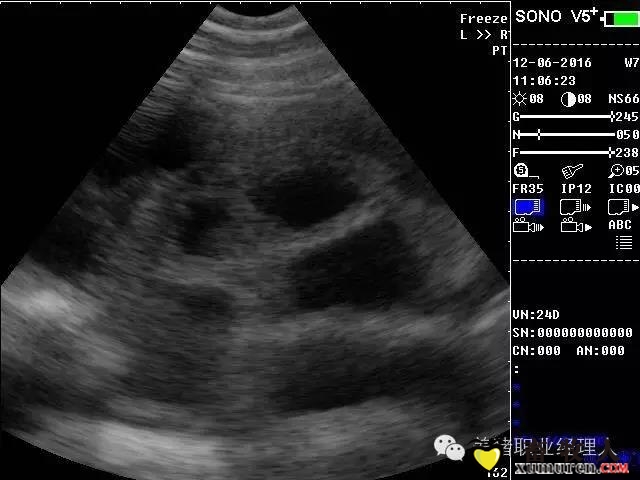

5.jpg

24天怀孕检测图